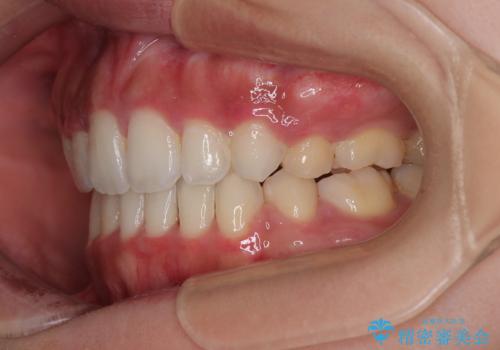

- 口元の突出感と口の閉じにくさを気にして来院された患者様です。

上下左右第一小臼歯4本を抜歯し、ワイヤー装置にて口元を引っ込めるよう矯正治療を行うこととしました。

口元の突出感が改善されてことで、下唇に引っかかっていた上顎前歯も気にならなくなりました。